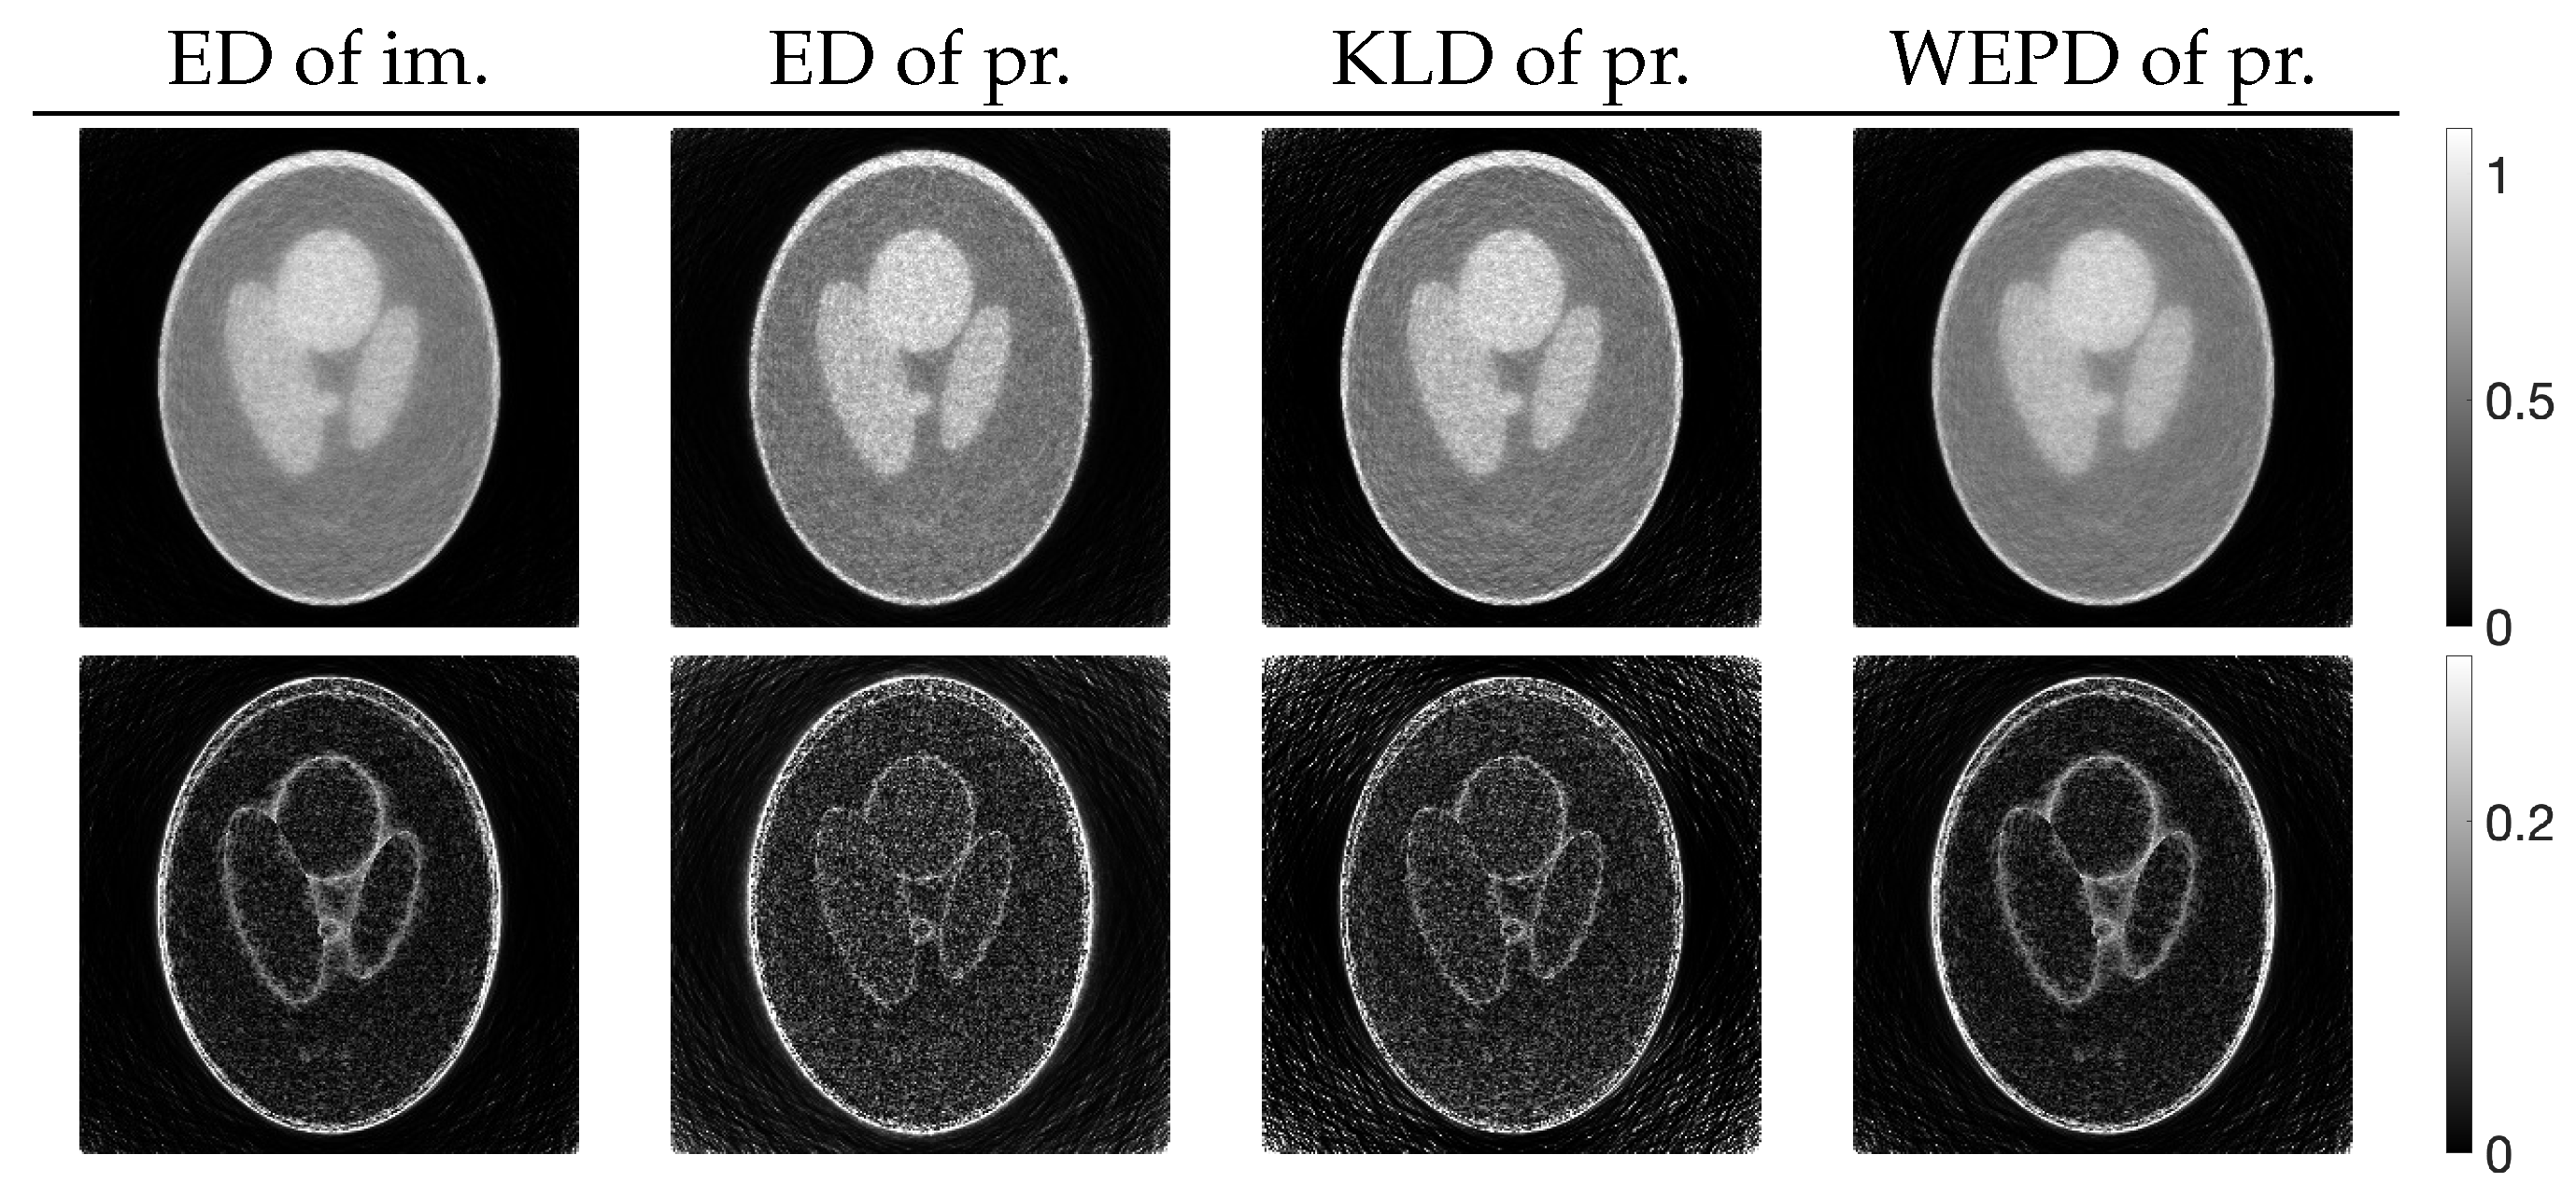

for , of images reconstructed by using PXEM with the parameter optimization functions defined in Equation (10) and Equations (14)–(16) as well as images using MLEM for comparison. Figure 12 (lower) plots the parameter changes for Equations (10) and (16). In the upper part of Figure 12, it is a well-known phenomenon that the function D with MLEM increases with a large number of iterations due to the relatively heavy noise added to the projections. On the other hand, with PXEM using Equation (16) based on the true image, the function value monotonically decreases as the number of iterations increases. Comparing the results of Equations (10), (14), and (15), which are functions of the measured and forward projections, reveals that only the case of Equation (10) exhibits a monotonic decrease. A visual assessment of the quality of the reconstructed images in Figure 13, as well as the evaluations using MS-SSIM and PSNR in Figure 14, confirms the superiority of the approach using Equation (10) for parameter optimization.

Change in with respect to the number of iterations n needed to reconstruct Shepp–Logan phantom using MLEM and PXEM with parameter optimization functions of Euclidean distance (ED) of images, ED of projections, KL-divergence (KLD) of projections, and weighted extended power divergence (WEPD) of projections (upper), and plot of parameters and for reconstruction using PXEM with Euclidean distance (ED) of images and weighted extended power divergence (WEPD) of projections (lower).

Figure 13.

Images reconstructed from Shepp–Logan phantom using PXEM with parameter optimization functions of Euclidean distance (ED) of images, ED of projections, KL-divergence (KLD) of projections, and weighted extended power divergence (WEPD) of projections (upper) and their subtraction images (lower).